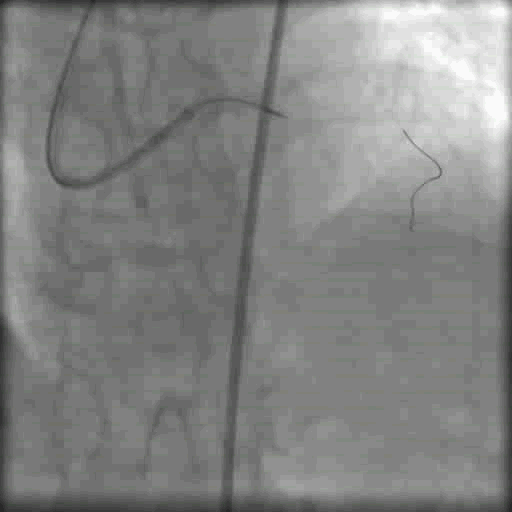

双侧造影显示闭塞段不长,右冠向左冠发出侧支循环供血,但是LAD闭塞段开口仍不清晰

通过双侧造影判断LAD 大致走形方向(图中箭头所示)